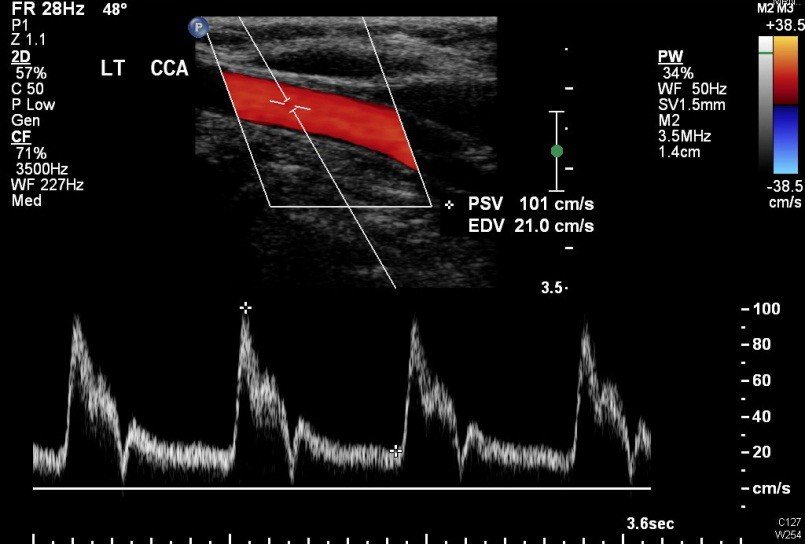

Color Doppler: Superimposes color-coded flow information on B-mode images.

Red and blue displays indicate direction and velocity of blood flow

Typically: red = flow toward transducer, blue = flow away

Color brightness/saturation indicates velocity magnitude

A color Doppler ultrasound of the left common carotid artery showing red coloration indicating blood flow toward the transducer, with the spectral waveform displayed below for quantitative analysis.